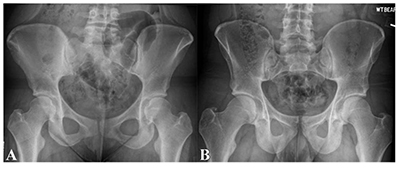

female male pelvis hip injuries bearing weight pelvic versus differences xray ap rays affect athlete injury specific function structure patterns